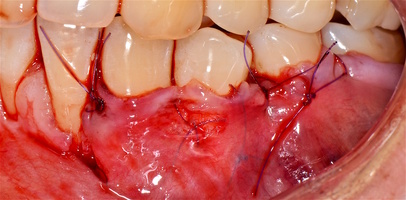

Участки 3.3-3.6 зубов и 4.3-4.6 зубов были проопери- рованы зеркально по методу коронально-ротированно- го лоскута по M. De Sanctis и G. Zucchelli (2000) с одним послабляющим вертикальным разрезом в области 3.3 зуба или 4.3 зуба.

Протокол хирургической операции:

1. Измерены глубины рецессий (ГР), эти замеры отложены от вершин межзубных сосочков в апикальном направлении в сторону зенита рецессии.

2. Дизайн разрезов соответствует методике Zucchelli G. коронально-ротированного смещения (2000).

3. Мобилизация слизисто-надкостничного лоскута, деэпителизация анатомических сосочков, обработка поверхности корней зубов.

4. Фиксация пластического материала ТМО (dura mater) к поверхности корней зубов в области зоны создания необходимого объема прикрепленной десны.

5. Закрытие пластического материала слизисто-надкостничным лоскутом со смещением в корональном направлении, и фиксация слизисто-надкостничного лоскута швами; дополнительная фиксация зоны перемещенных и в будущем созданных мягких тканей десны в зоне рецессии десны для стабилизации результата операции.